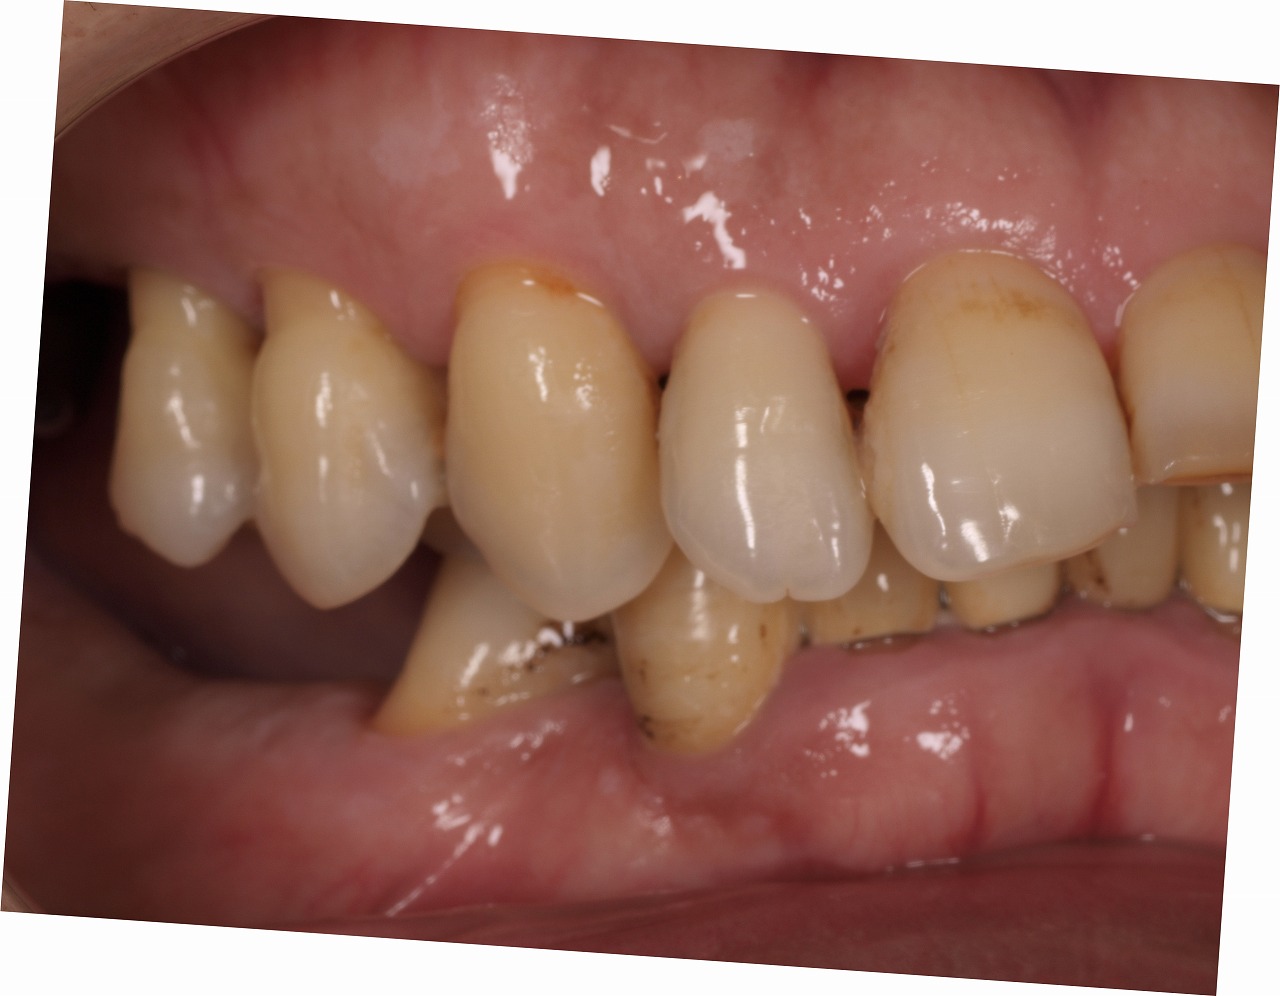

欠損部へインプラントを用いた咬合再構成|お知らせ |広島市安佐南区の歯科医院 欠損部へインプラントを用いた咬合再構成 トップ お知らせ・ブログ お知らせ 欠損部へインプラントを用いた咬合再構成 欠損部へインプラントを用いた咬合再構成 術前のパノラマになります 初診時の口腔内 右側面観 切歯部 左側面観と上顎の咬合面観 下顎の咬合面観 インプラント術後のパノラマになります 大きくすべての歯を仮歯に置き換えていきます 咬合挙上と咬合平面などの修正を加えていきます 部分的に最終補綴に置き換えていきます Web診療予約 初めての方へ 選ばれ続ける理由 院内設備について 歯が痛いしみる一般歯科 歯がぐらぐらする歯周病 健康な歯を保ちたい予防歯科 子供の虫歯予防をしたい小児歯科 銀歯をセラミックに審美歯科 白い歯を目指しませんか?ホワイトニング 矯正専門医がいるので安心矯正歯科 抜けた歯を補いたいインプラント・入れ歯 医院案内 スタッフ紹介 メリィハウス歯科クリニックオフィシャルホームページ ラベンダー歯科クリニックオフィシャルホームページ お知らせ・ブログ ホーム 診療科目 一般歯科 歯周病治療 予防治療 小児歯科 審美治療 ホワイトニング 矯正歯科 入れ歯・インプラント マウスピース矯正 初めての方へ 院長・スタッフ 設備紹介 医院案内・アクセス メニューを閉じる